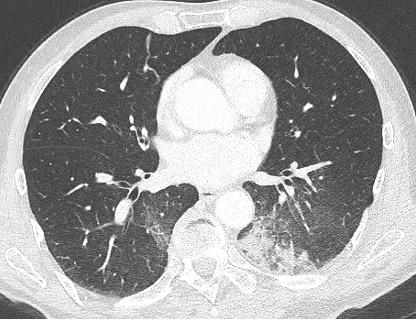

Entraînez-vous à lire des radios en vous appuyant sur des corrélations radio-scanner! Découvrez le site d'auto-apprentissage de la radiographie thoracique